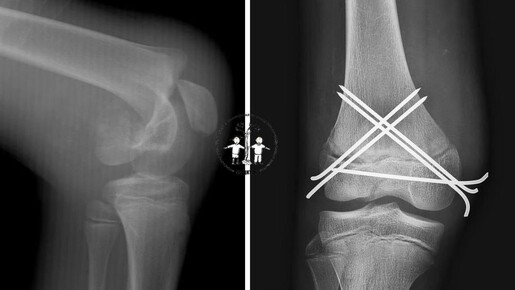

Врачи Московской областной детской клинической травматолого-ортопедической больницы спасли 16-летнего подростка, упавшего с кроссового мотоцикла. Юноша потерял управление из-за заклинившей педали газа. Специалисты обследовали пострадавшего и выявили у него перелом бедренной кости, что потребовало срочного вмешательства. Сначала хирурги вернули отломки в правильное положение. «Это было необходимо для правильного сращивания кости и восстановления анатомической функции ноги...